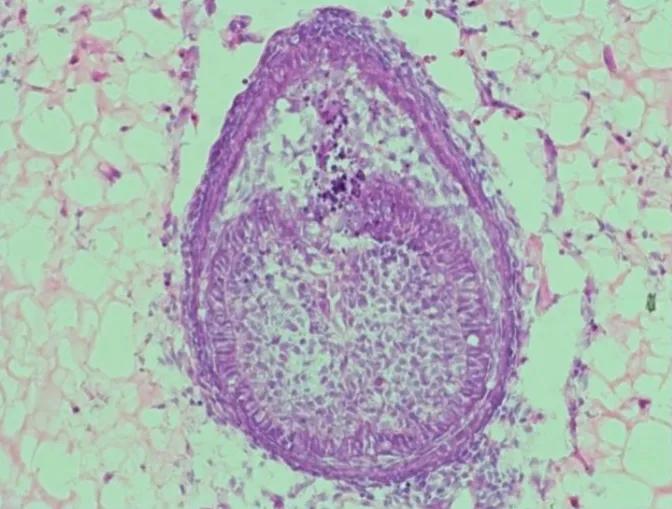

据美媒报道称,伦敦国王学院再生牙科研究生院院长安娜·安杰洛娃·巴尔波尼 (Ana Angelova Balponi) 在她的实验室里进行了大约 20 年的牙齿培养实验。 他是 2013 年使用人类和小鼠细胞成功培养牙齿的团队的一员。 今年,根据这些结果,巴尔波尼的研究在实验室种植牙齿的材料方面取得了突破。 这种材料更好地模仿了生物牙齿在口腔中实际生长的环境。 这是用人类细胞替代小鼠细胞的重要一步,人类细胞会刺激它们形成牙齿。 根据 Balponi 的说法,在实验室培养牙齿的想法可以追溯到 1980 年代。 他和他的同事十多年前开发的牙齿最初是通过将成人牙龈细胞与取自小鼠胚胎的“祖先”牙齿细胞相结合而制成的(是的)。 Balponi 将实验室环境中长牙的元素比作“像三脚架”。 “两种类型的细胞在交换对话之类的东西时会产生牙齿,我们已经准备了一个环境来实现这一目标。” 研究人员称之为“脚手架”的环境对于在实验室中培养牙齿至关重要。 Balponi 将此作为他的最新研究主题。 13岁时,他使用由胶原蛋白(一种蛋白质)制成的支架,但现在他使用水凝胶,一种含水量高的聚合物。 据伦敦国王学院博士生、该研究的合著者薛晨江介绍,“首先,从小鼠胚胎中收集细胞,混合在一起,然后离心制成小细胞沉淀。 该研究侧重于环境,因此不需要人体细胞。 8天后,在水凝胶中形成齿状结构。 在一项为期 13 年的研究中,这种“牙齿原基”被移植到小鼠体内,并发育成牙根和牙釉质生长的牙齿结构。 在实验室生长的牙齿被人类使用之前,还有很多挑战。 尽管如此,这种新材料仍然可以通过改善制造牙齿的细胞之间的“对话”来帮助解决问题。 巴尔波尼说。 研究人员仍然不知道如何用成体细胞替代小鼠胚胎细胞,但一旦解决了这个问题,Balponi 有两种方法将实验室生长的牙齿融入日常牙科护理中。 一种是将牙齿长到一定的发育阶段,然后将它们植入缺牙的地方(牙槽腔)。 另一种是将牙齿完全长出来,然后通过手术种植。 Balponi 指出,现在确定哪种方法更现实还为时过早。